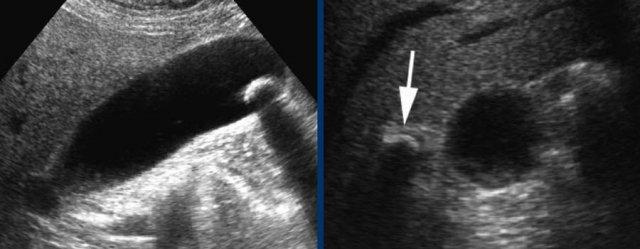

Ngay cả trong trường hợp có nhu mô gan xen giữa thành bụng và túi mật, vẫn có thể chứng minh được dấu hiệu “phình to túi mật gián tiếp”.

Hình bên trái cho thấy túi mật duy trì hình dạng tròn, cả trước và trong khi ấn đè, đồng thời phồng lên vào nhu mô gan mềm xen kẽ và thành bụng.

Tương tự, sự vắng mặt của dấu hiệu phình to túi mật cũng có thể được chứng minh, ngay cả khi có nhu mô gan xen giữa, vốn mềm mại khi ấn đè (hình bên phải).